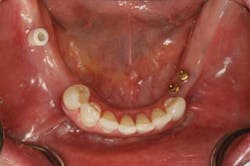

In my practice, being able to identify what I call the "stinkers," or hidden caries that on the surface appear tiny but can turn into schedule wrecking near root canal disasters, is nothing short of a lifesaver. Man, how I hated explaining to patients why what we scheduled as a simple class I composite had become a root canal, core, and crown, or a similar variation (Fig. 2).